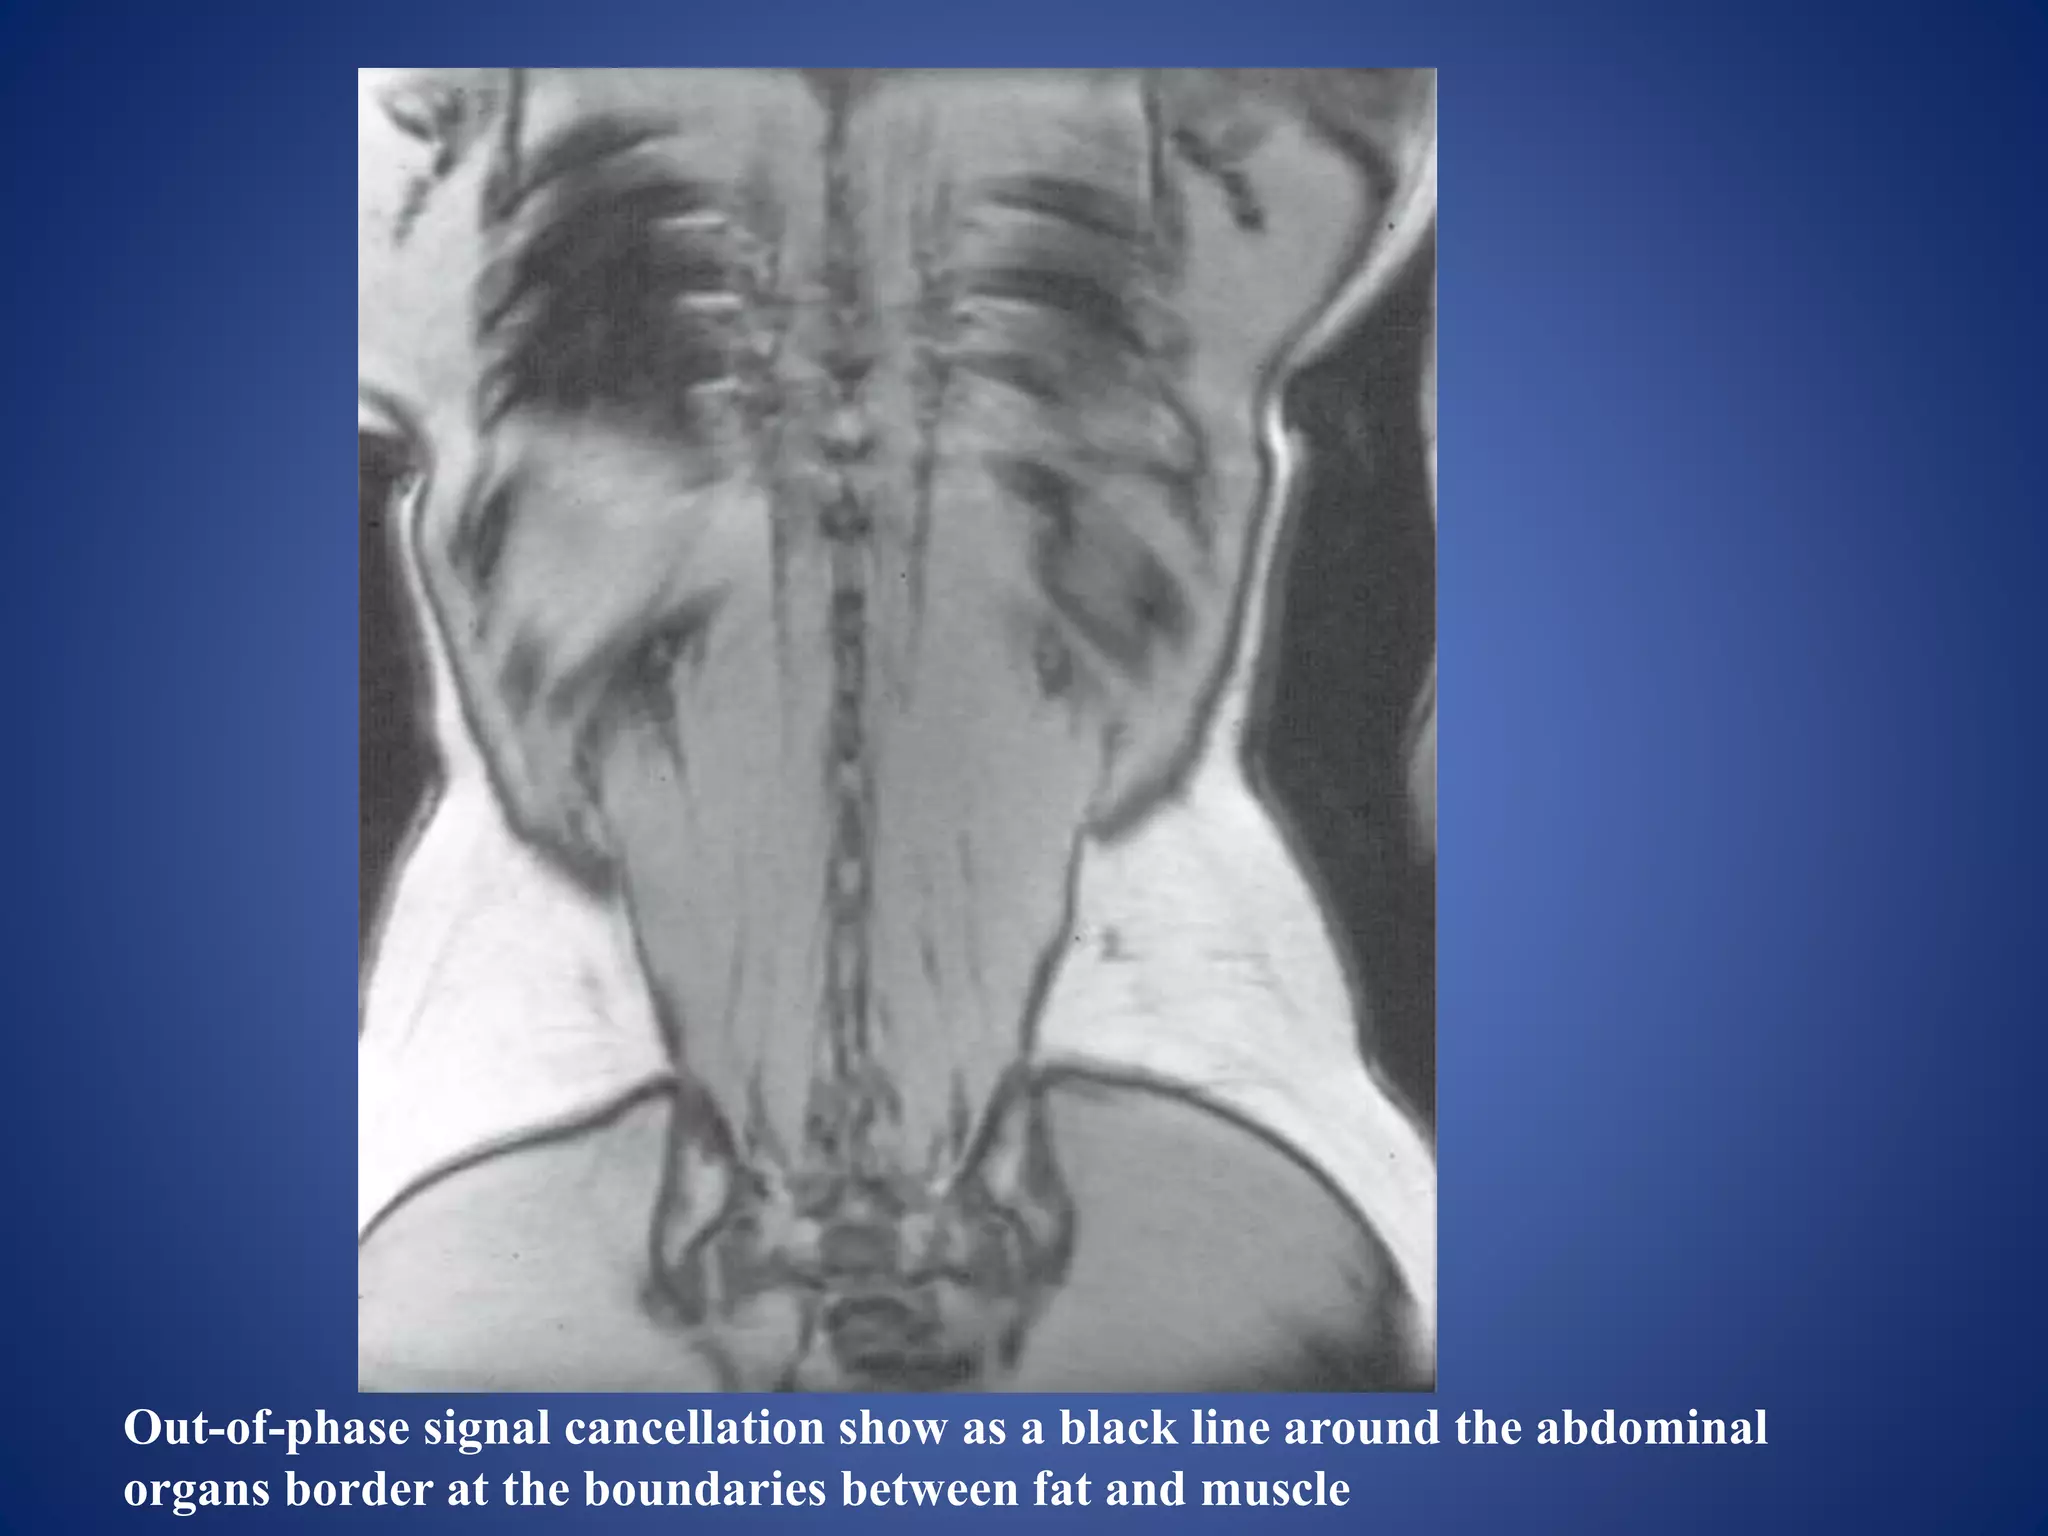

Out phase signal cancellation artifacts

• Appearance: produces a ring of dark signal

around certain organs where fat and water

interfaces occur within the same voxel.

 It degrades the image in gradient-echo pulse

sequences because gradient rephasing does not

compensate for this artifact.

• Cause:

• caused by the fact that the magnetic moments of

hydrogen precess at different frequencies, and the

differences in their phase positions are exhibited

by fat and water vectors at discrete points in time.

Out-of-phase signal cancellation show as a black line around the abdominal

organs border at the boundaries between fat and muscle